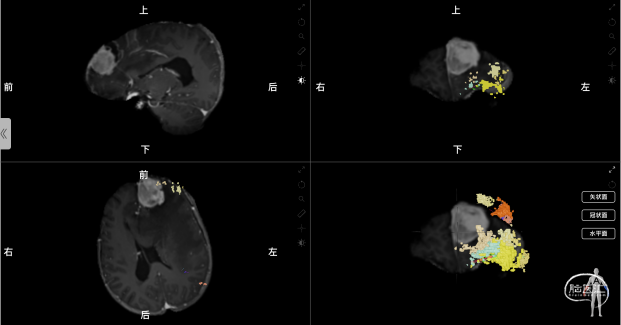

术前采用Nura Surgical脑网络重建分析

使用解剖像磁共振数据+DTI成像,基于Nura Surgical的独特算法追踪全脑的白质纤维束,并使用技术进行个体化的大脑重新分区,生成关键大脑结构网络。根据肿瘤与关键白质纤维束及功能网络的关系,确定收到肿瘤影响最为严重的大脑结构网络为中央执行网络,受到肿瘤影响最为严重的关键关键白质纤维束为皮质脊髓束。其中,中央执行网络的额叶部分与肿瘤关系密切,分布在肿瘤的外下方,应考虑在手术中进行保护。皮质脊髓束没有受到肿瘤直接影响,但受到肿瘤引起的水肿导致患者皮质脊髓束明显被推挤向后移位,预估术后可部分恢复,对患者运动功能影响不大。

图2 术前使用Nura Surgical重建肿瘤与中央执行网络的关系,中央执行网络显示为黄橙色的彩色体素颗粒和彩色白质纤维束线条组成的整体(左上:矢状位;右上:冠状位;左下:轴位;右下:3D重建。)